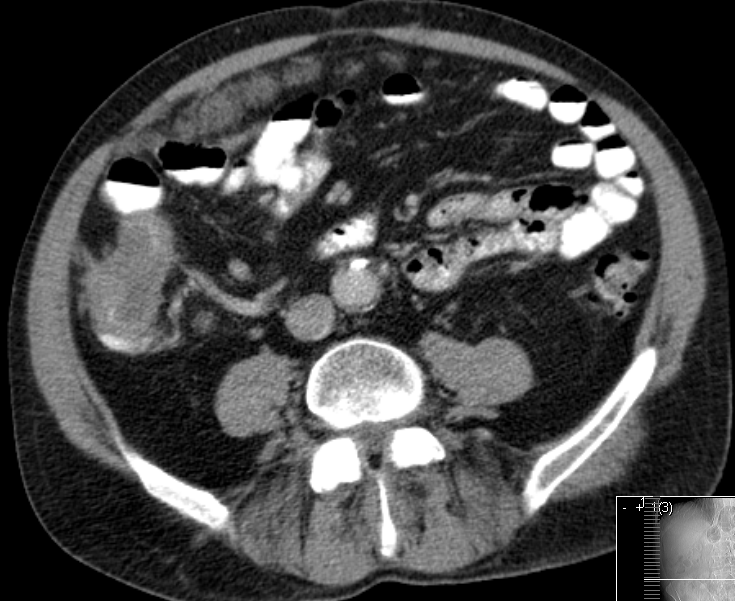

| Beispiele bildgebender Diagnostik von primären Colonkarzinomen | Zökum |

mesenteriale Metastasierung |